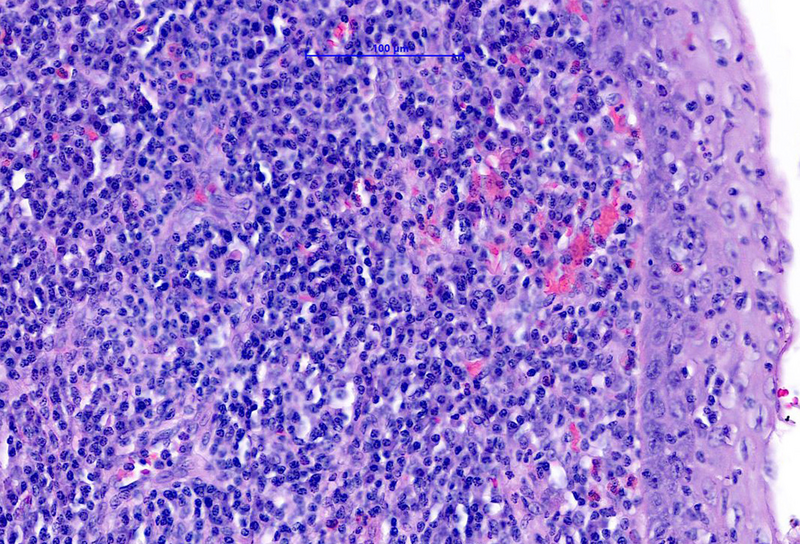

The microscopic examination of the resection specimen revealed diffuse lymphoplasmacytic infiltration throughout the oesophageal wall, with multiple lymphoid follicles and accentuation within the inner half (Panel A). On high magnification, diffuse infiltration of the overlying squamous epithelium by lymphocytes („lymphocytic oesophagitis pattern of injury”) and occasional plasma cells was observed (Panel B). The plasma cells were strongly positive for IgG and IgG4 (Panels C-D).

Morphologically, IgG4 positive, dense, lymphoplasmacytic infiltrate is visible, with >10 plasma cells per high-power field. The elevated ratio of IgG4/IgG (>40%) is observed, as well. Furthermore, storiform fibrosis, and obliterative phlebitis may be seen, although these features may not be present on small biopsy specimens. At least 2 of the above mentioned criteria results in the definitive diagnosis of IgG4-related disease. Differential diagnosis on small biopsies includes lymphocytic oesophagitis.